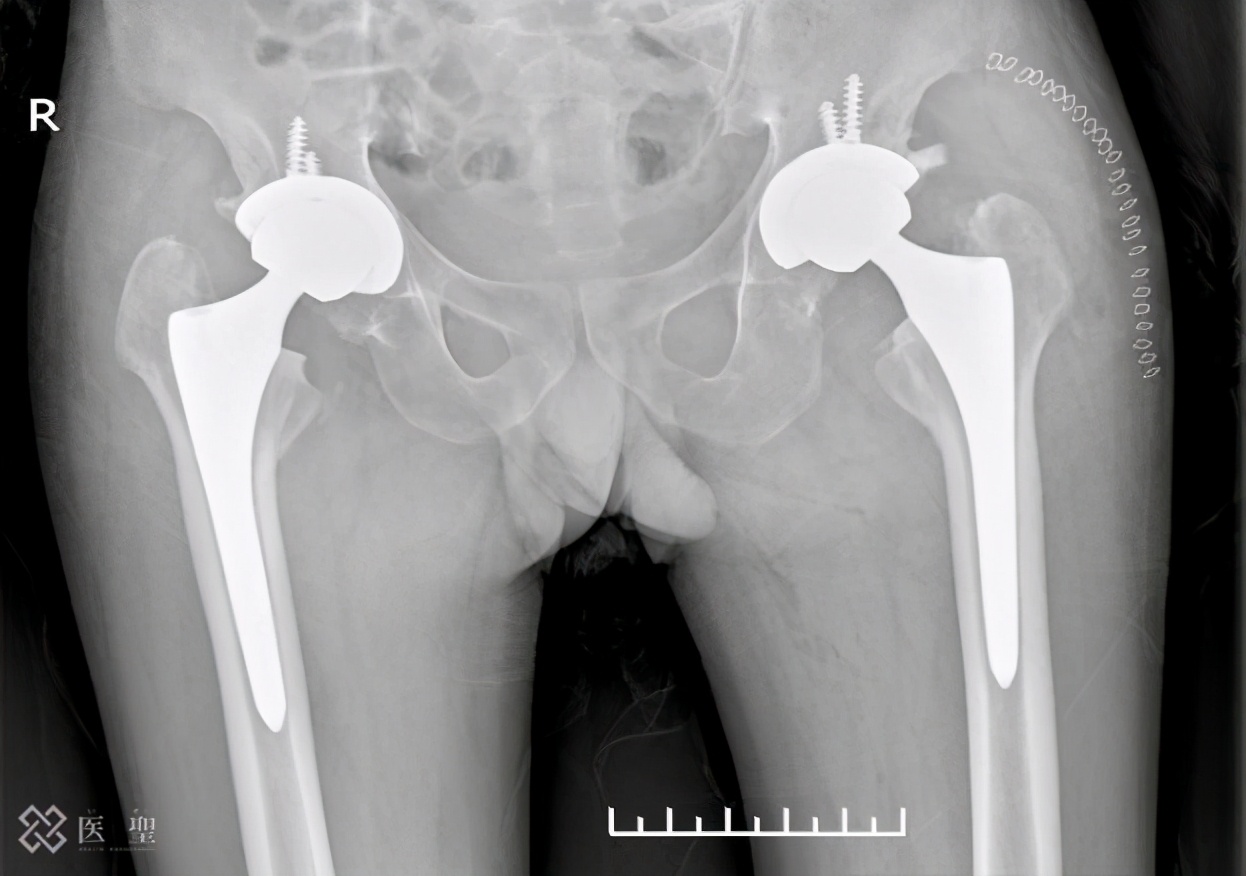

作为股骨头坏死的手术疗法,大致可以分为保存自己的髋关节的方法和用人工物置换髋关节的方法。 髋关节是支撑自己体重的重要关节。 坏死的部分承受体重的话,股骨头会变坏,所以在保存自己的髋关节的手术方法中,以向健康的部分施加体重负荷的方式移动为目的。

如果股骨变形到无法进行这种处理的程度,就用人工物置换髋关节。 因为将髋关节置换为人工物,所以耐久性有限,将来有必要再次手术。 因此,要慎重考虑人工髋关节置换术的适应。

髋关节置换